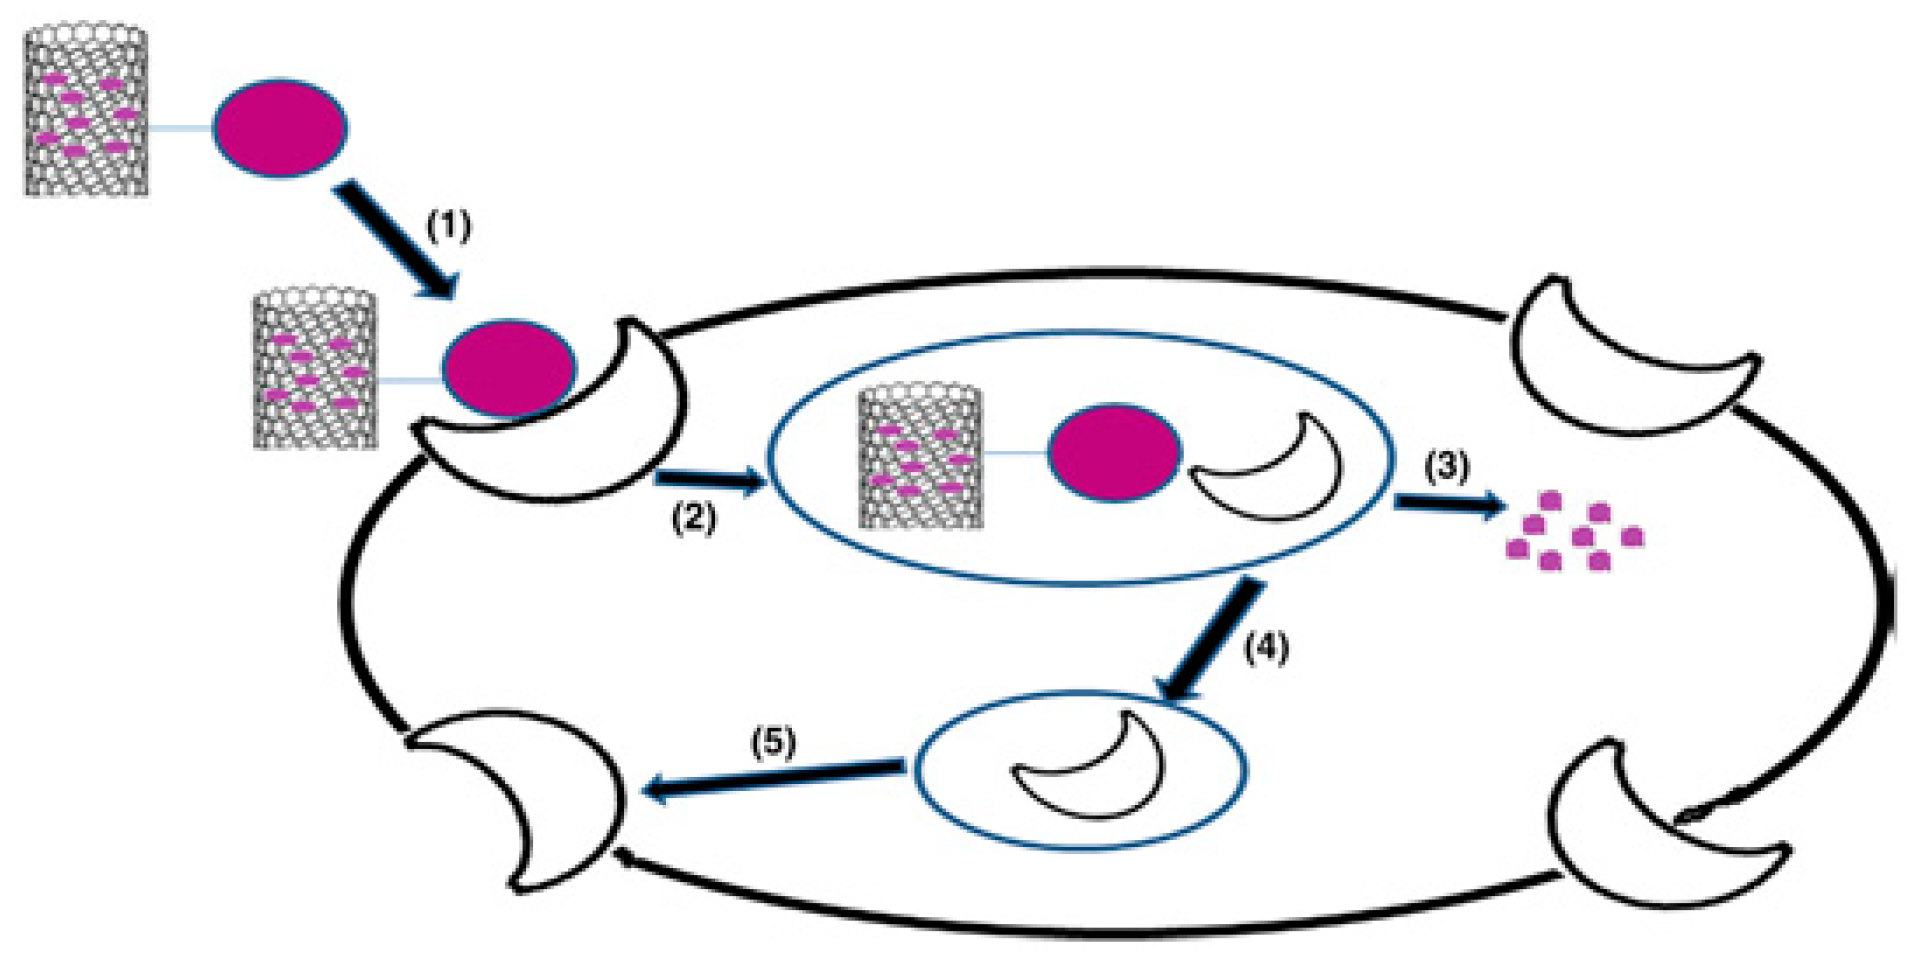

2.2.1. Carbon Nanotubes

3.1. Carbon Nanotubes

4.2. Carbon Nanotubes

4.3. Super Paramagnetic Iron Oxides NPs